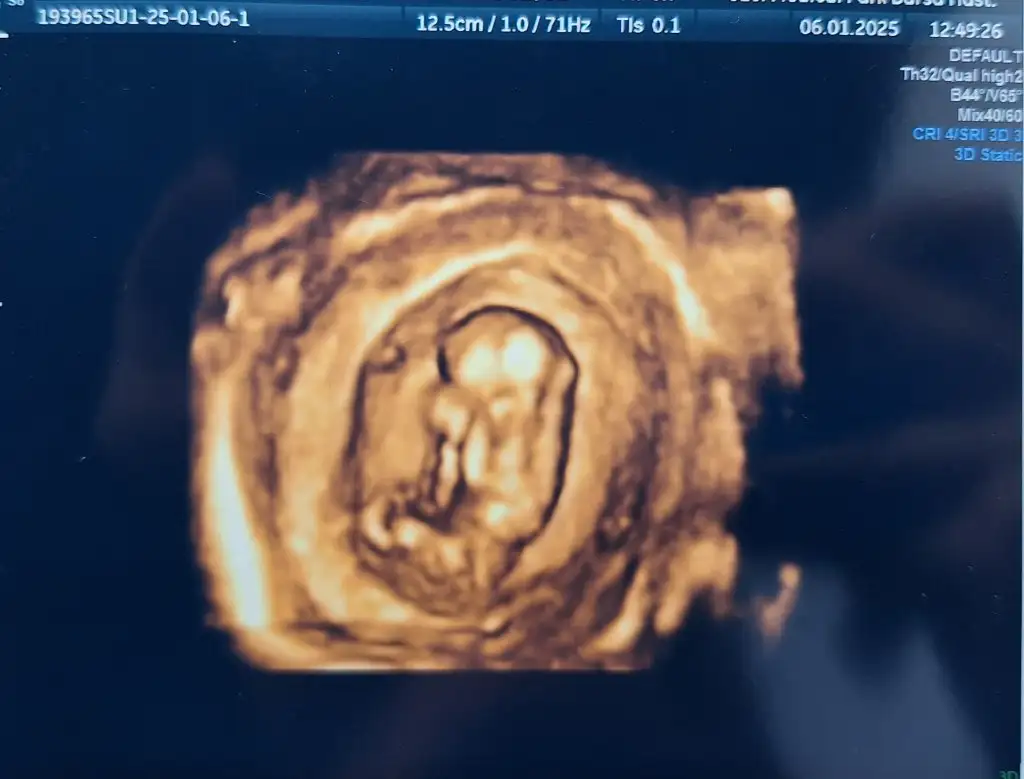

Bugünkü (10+3) karından yapılan ultrasonumda cinsiyet tahmini yapabilecek olan varsa düşüncelerinizi öğrenebilir miyim ☺️ Hayırlı,sağlıklı olsunda cinsiyeti önemli değil ama insan merakta ediyor tabi 🤭